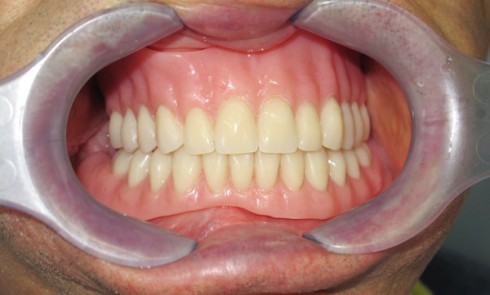

La demande esthétique des patients ne cesse de progresser et se traduit par une augmentation du nombre de consultations ayant...

Odontologie restauratrice